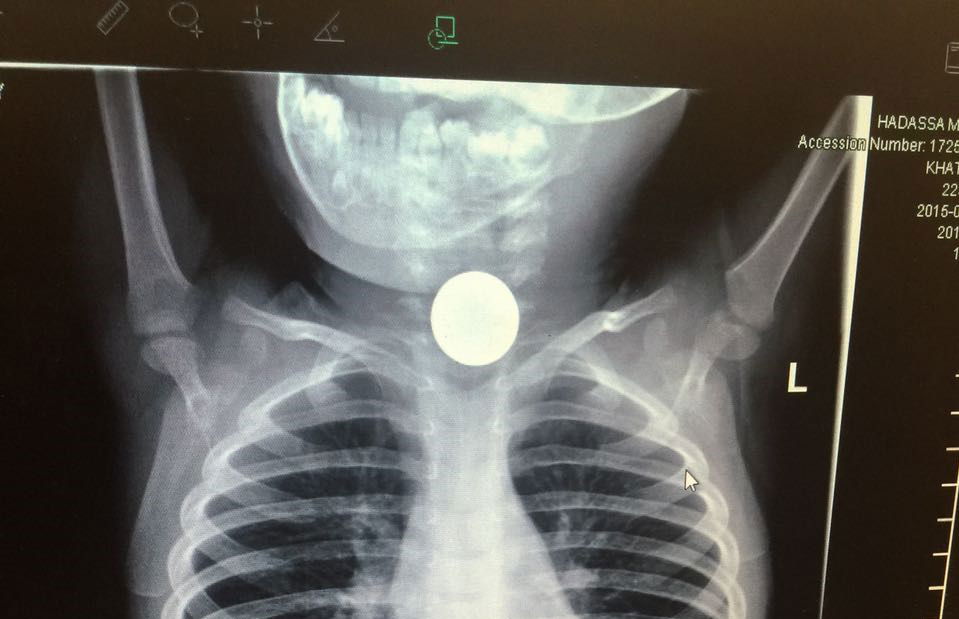

סדרת בדיקות ובכללן בדיקת רנטגן הבהירו ללא כל צל של ספק כי חפץ עגול ושטוח היה נעוץ בוושט של הפעוט. ד"ר מרדכי סליי, רופא גסטרו ילדים בכיר הוזעק בדחיפות למיון ילדים והחל בפעולות חילוץ מידיות של החפץ אשר עלול היה לגרום לסיבוכים ניכרים עד כדי התערבות ניתוחית ואף לסיכון חייו של הילד.

"היה ברור כי הילד במצוקה" אמר ד"ר סליי. "על מנת לבצע את הפרוצדורה, היה צורך להרדימו. החפץ גלש לקיבה ומשם שלפנו אותו בזהירות רבה. אז התברר כי הפעוט בלע מטבע של עשר אגורות, כאשר אף אחד לא שם לב".